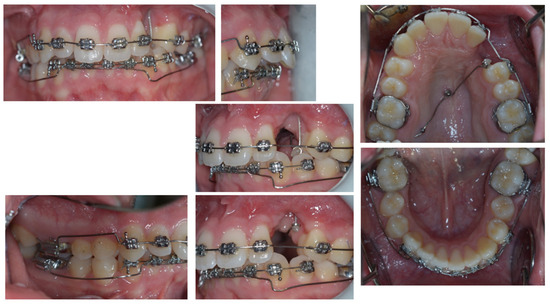

4. Follow-Up and Outcomes